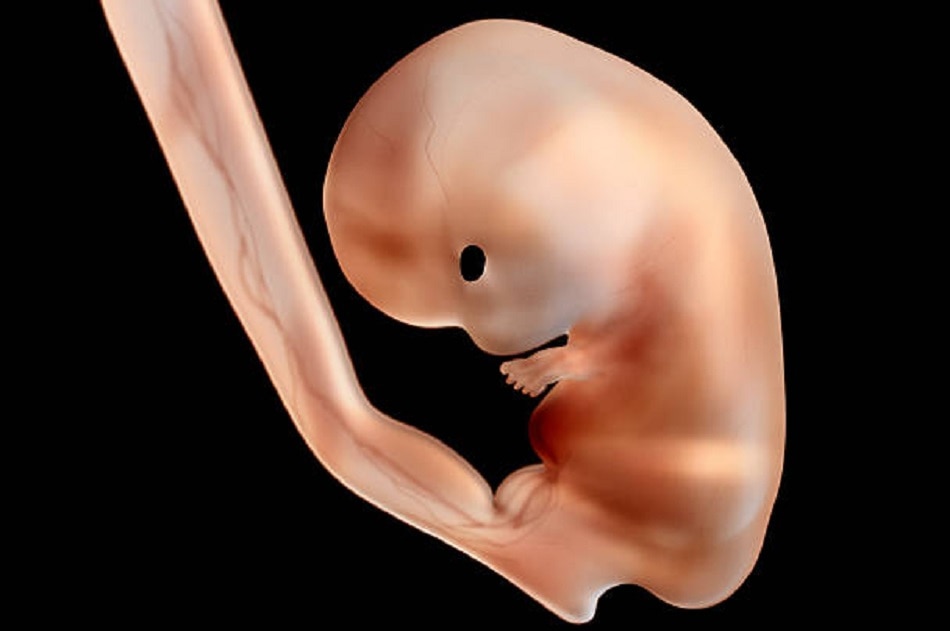

अब सवाल उठता है कि जब फर्टिलाइजेशन का तरीका वही है तो ये कैसे तय होता है कि भ्रूण लड़के में तब्दील होगा या लड़की में? आमतौर पर किसी महिला को एक महीने बाद प्रेग्नेंसी का अहसास होता है. तब तक शरीर में भ्रूण बन चुका होता है जिसका आकार 6 मिलीमीटर यानी मटर के दाने से भी आधा होता है. इस वक्त तक भ्रूण की गर्दन और हाथ-पैर बनना शुरू हो जाते हैं.

छठे से सातवें हफ्ते के बीच भ्रूण करीब एक सेंटीमीटर जितना बड़ा हो चुका होता है. यानी बिल्कुल मटर के दाने के बराबर. इस दौरान सेक्स ग्लैंड्स या रीप्रोडक्टिव ग्लैंड्स का विकास हो चुका होता है. लड़का या लड़की दोनों में ये ग्लैंड शुरुआत में बिल्कुल एक जैसे ही होते हैं. इन ग्लैंड से टेस्टीज़ बन सकती हैं जो कि टेस्टोस्टेरॉन नाम का हार्मोन रिलीज करती है. लड़कों के लिंग का विकास इसी वजह से संभव हो पाता है.